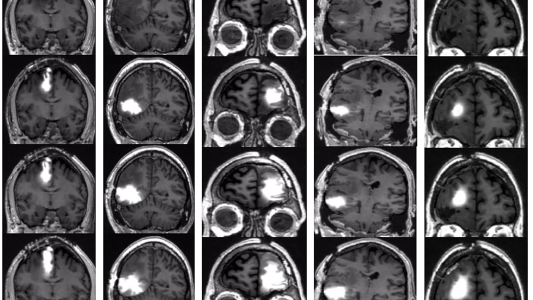

New brain cancer vaccine completes clinical trial

Northwest Biotherapeutics reports that its new brain cancer vaccine can extend glioblastoma patients’ lives by months or even years.

New chemo pump for brain tumors could avoid side effects

A fully implantable chemo pump could help extend the lives of people with deadly brain tumors while minimizing treatment side effects.